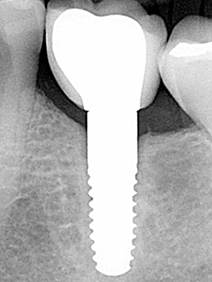

IMPLANTE CERÁMICA

Implantes dentales de cerámica: tan natural y estético como la naturaleza.

Desde los años setenta se intenta fabricar implantes dentales libres de metal con la ayuda de materiales cerámicos. Un gran avance se consigue con las máquinas de fresado guiado por ordenador CAD/CAM capaces de trabajar la extrema dureza de la cerámica dióxido de circonio.

Desde 2006 usamos implantes de circonio con gran éxito.